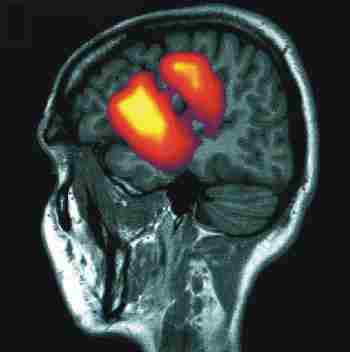

Das Bild rechts zeigt die Überlagerung eines Kerspintomogramms (grau) und einer Messung der durch Hirnströme verursachten Magnetfelder (Magnetenzephalographie). Mit dieser Methode kann die Aktivität in spezifischen Arealen des Gehirns definierten Tätigkeiten zugeordnet werden. Die räumliche Auflösung ist bei der Magnetenzephalographie ca 5 mm, und die Methode bietet eine sehr hohe zeitliche Auflösung, so daß auch schnelle, insbesondere rhythmische Aktivitätsmuster von Neuronen erfasst werden können.

Aus: Forschen in Jülich, 1/2000, Forschungszentrum Jülich